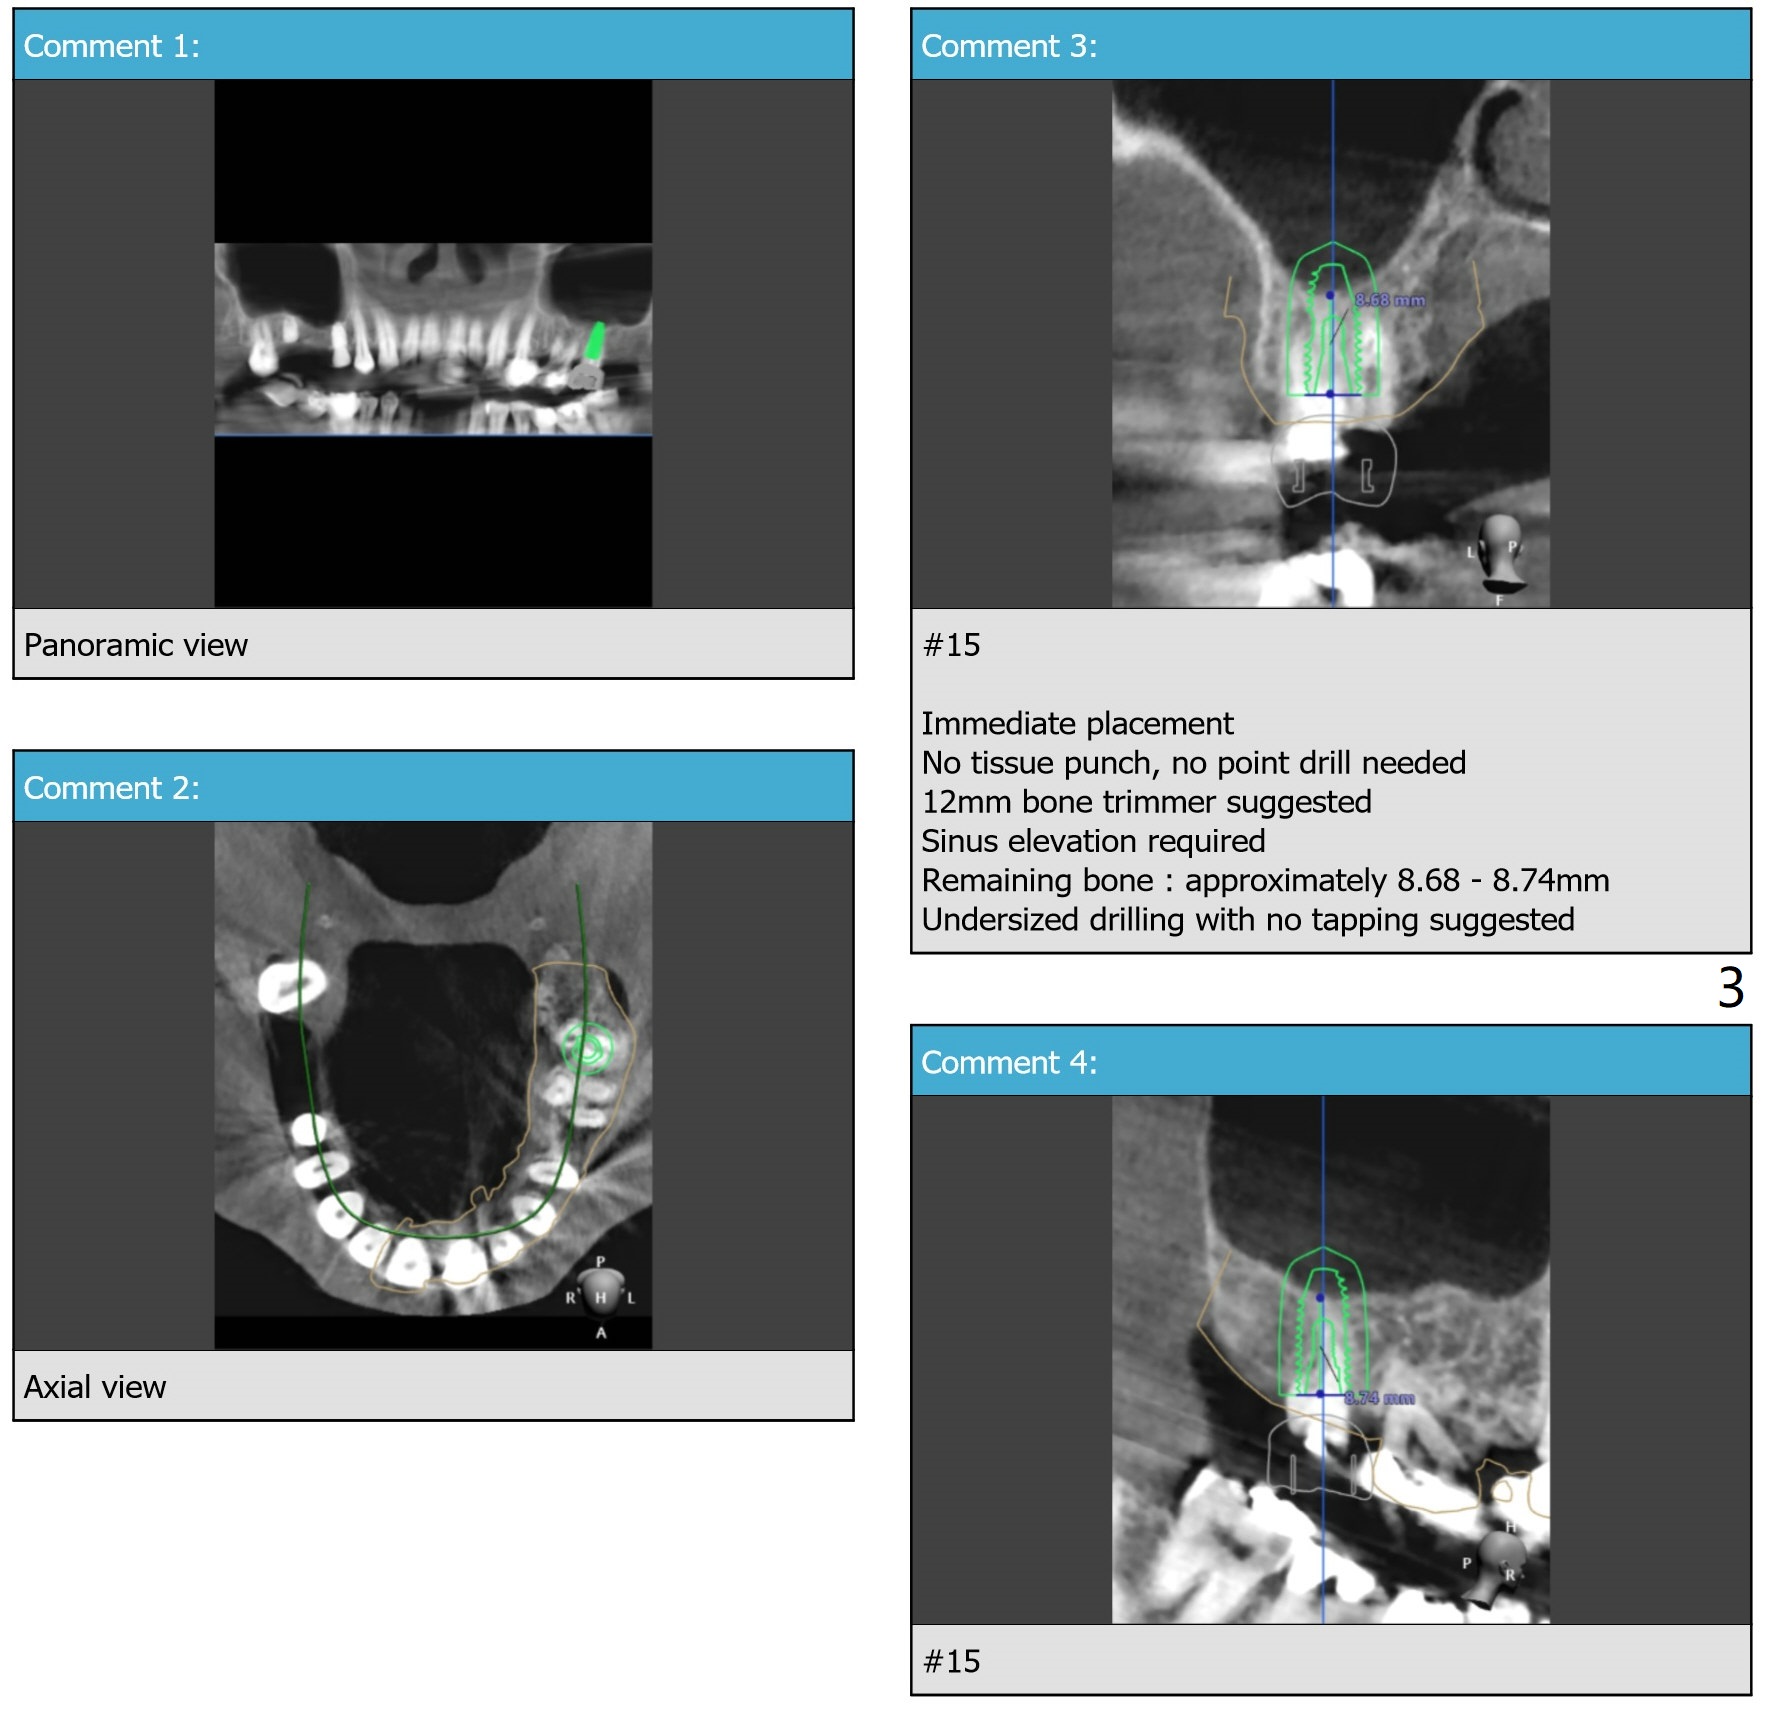

Limited Apical Bone-Sinus Lift

Return to Upper Molar Immediate Implant, Trajectory II, Clindamycin